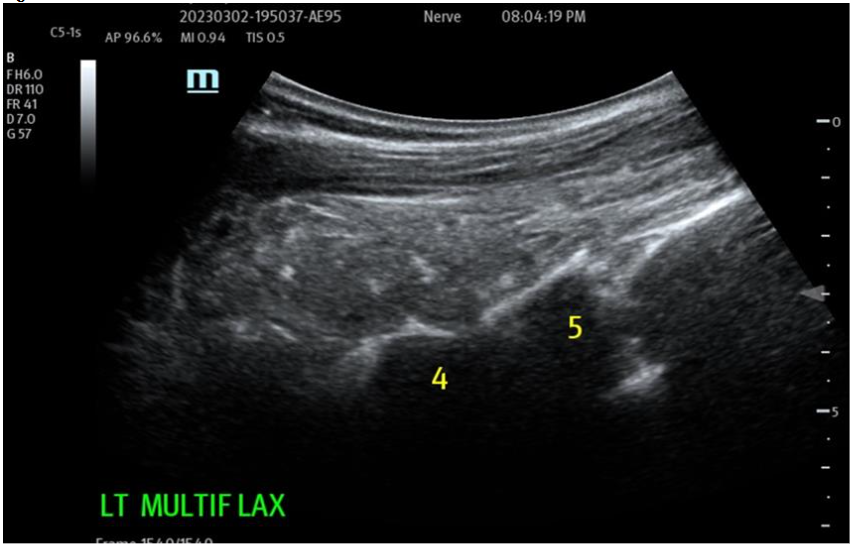

Figure 2: Use of sterile field Ultrasonographic Imaging for diagnostic and therapeutic Targeting of supportive structures Tissue Remodeling: The Biocellular contributions, with the synergy provided, between the addition of blood-derivatives (growth factors and cytokines/chemokines) and the stem/stromal complex, with its ECM scaffolding interact WITH the damaged or degenerative sites directly. This facilitates the repair of tissues in concert with the local existing microenvironments to help remodel and regenerate damaged, aging and degenerative structures. This impact is potentially seen to be helping slow down, or reverse, damaged/degenerative processes and assisting the needed healing processes per se. This is a result of both inflammatory modulation, immune protection and revascularization + perfusion improvements. More detail is beyond the scope of this Chapter, but is available in the peer-reviewed literature.

Figure 3A: Pre-operative treatment site Multifidus (loss of function dynamically) at L4-5 and above. Multiple targets IM for return of function and architecture. NOTE: Likely most common site that accompanies Lumbar facets pain seen together and is treated. Figure 3B: Post-Biocellular treatment (18 mon.) Piriformus Syndrome.